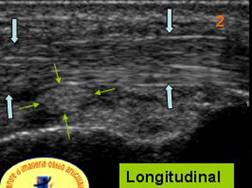

Se traduce ecografic printr-o ingrosare fuziforma a tendonului, centrata de o placa de dezorganizare a fibrelor de colagen care ia un aspect de placa hipoecogena nodulara pe sectiunile axiale si fuziforma pe sectiunile sagitale. Acest nodul se situeaza pe fata profunda a tendonului respectand fibrele superficiale. Prezenta unei vascularizatii de neoformatie reactionala in jurul si pe fata posterioara a nodulului indica cicatrizarea leziunii.

Clinic – punct dureros in mijlocul patelei Ecografic, insertia proximala a tendonului patelar este semnul unui epansament centrat pe un nodul hipo ecogen cu respectarea fibrelor superficiale si prezenta unei hiper vascularizatii periferice la doppler color.

TENDINOPATIA ROTULEI

Ingrosarea fuziforma a insertiei rotuliene

A tendonului patelian centrat de un nodul

hipervascularizat